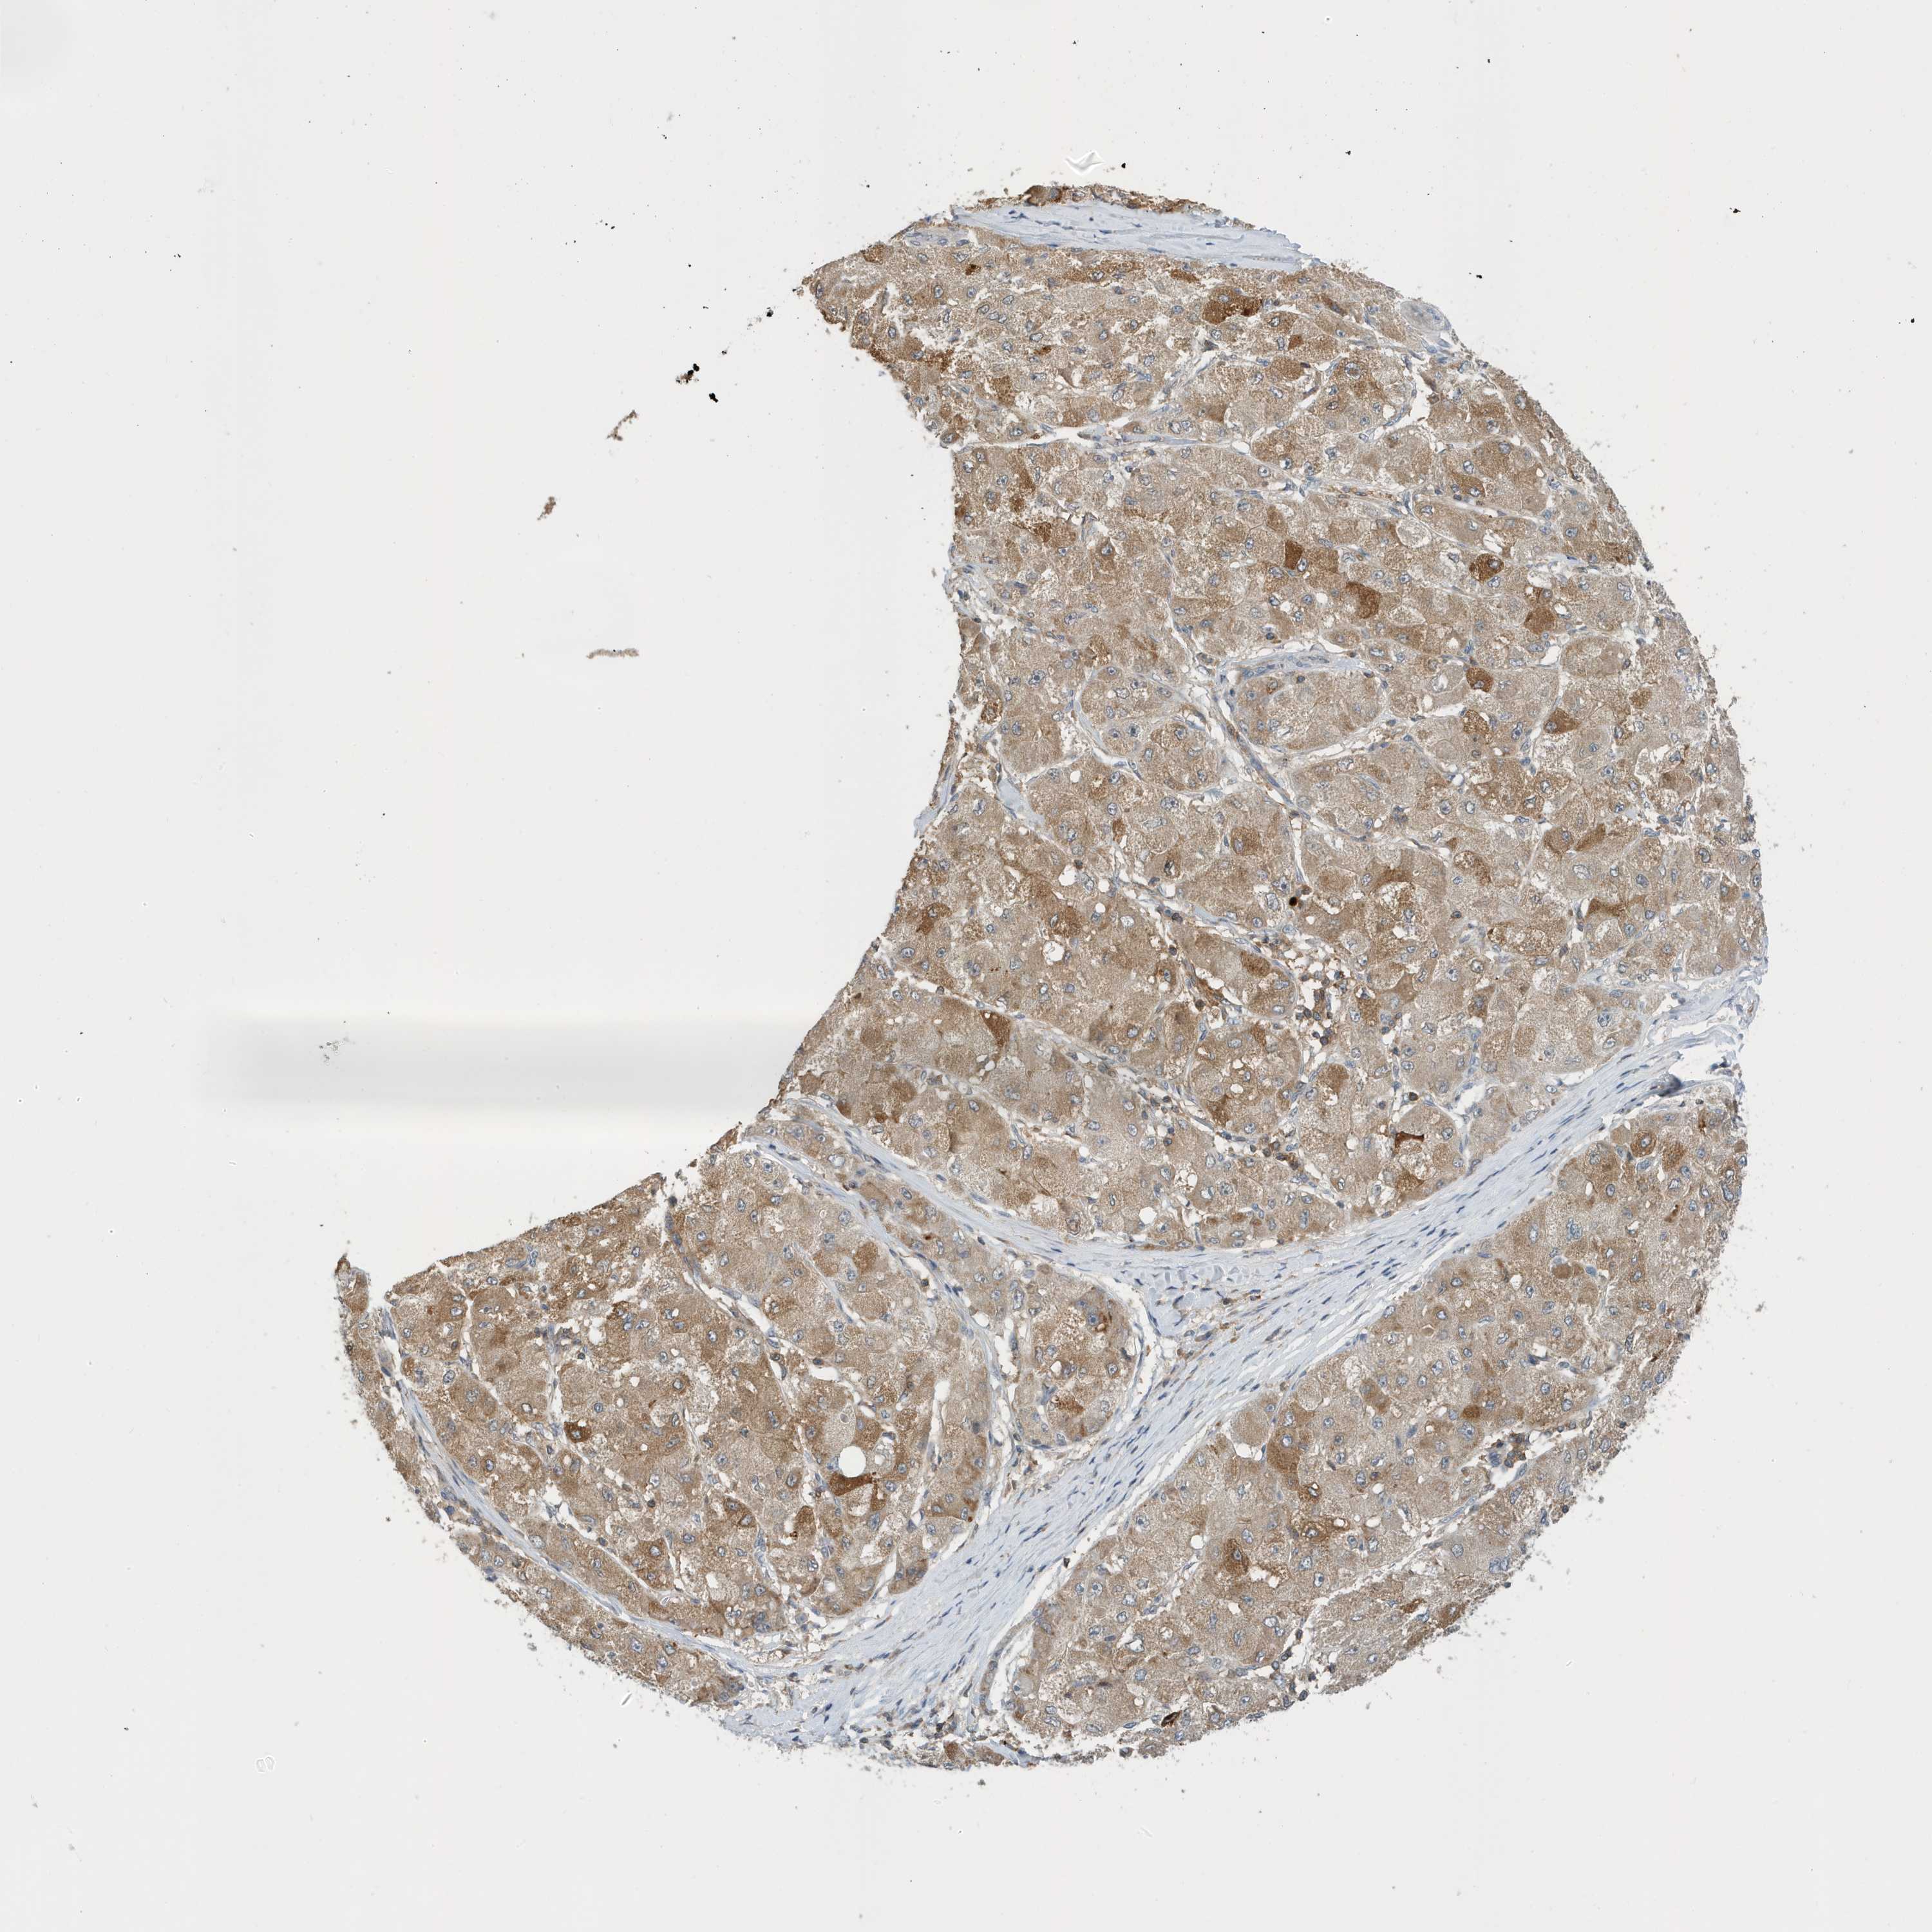

LIVER CANCER - Protein expressioni

A mouse-over function shows sample information and annotation data. Click on an image to view it in a full screen mode. Samples can be filtered based on level of antibody staining by selecting one or several of the following categories: high, medium, low and not detected. The assay and annotation is described here.

Note that samples used for immunohistochemistry by the Human Protein Atlas do not correspond to samples in the TCGA dataset.

Antibody stainingi

Antibody staining in the annotated cell types in the current human tissue is reported as not detected, low, medium, or high, based on conventional immunohistochemistry profiling in selected tissues. This score is based on the combination of the staining intensity and fraction of stained cells.

Each image is clickable and will lead to virtual microscopy that enables deeper exploration of all samples and also displays staining intensity scores, fraction scores and subcellular localization as well as patient and tissue information for each sample.

Antibody HPA036181

Staining

High

Medium

Low

Not detected

Intensity

Strong

Moderate

Weak

Negative

Quantity

>75%

75%-25%

<25%

None

Location

Nuclear

Cytoplasmic/membranous

Cytoplasmic/membranous,nuclear

Cholangiocarcinoma

Carcinoma, Hepatocellular, NOS